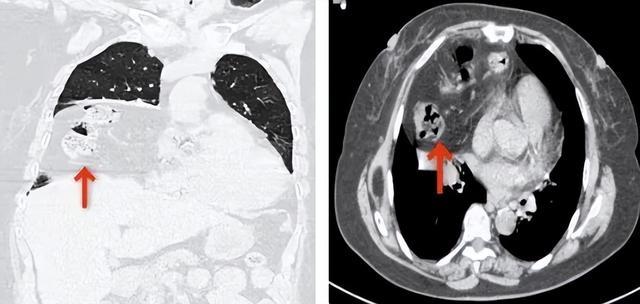

(▲术前CT可见部分肠管疝入右侧胸腔(箭头所示),导致右肺明显受压萎缩)

术后,李奶奶恢复良好,呼吸困难症状消失,在不吸氧的情况下,血氧饱和度稳定在95%以上,现已康复出院。